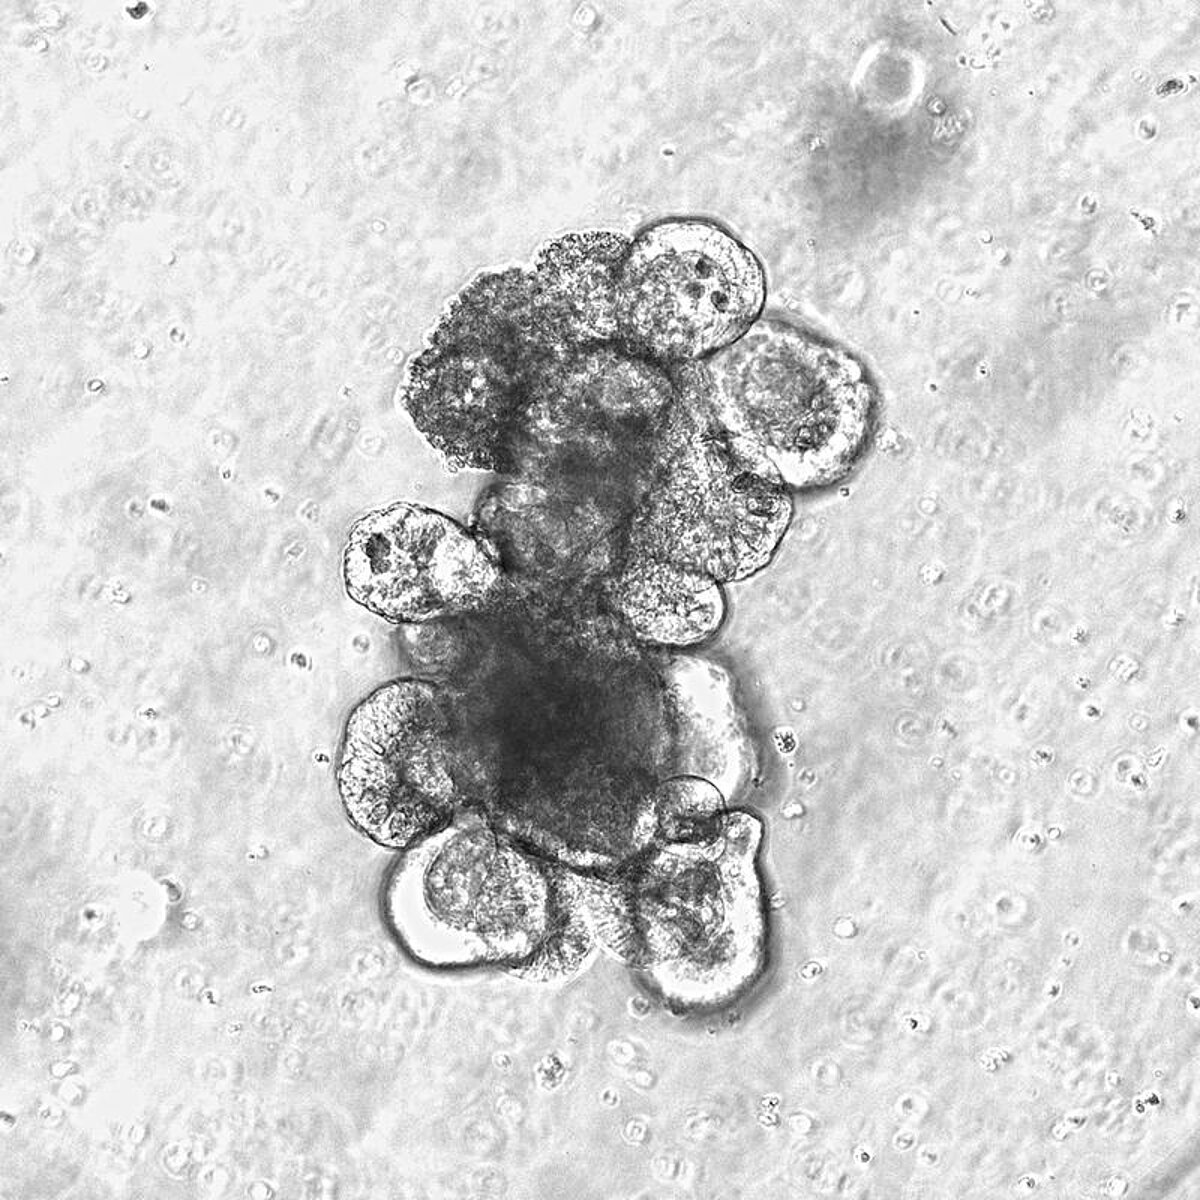

Modern organoid cultures - small “mini-intestines” - are made from human stem cells in the laboratory. Sascha Göttert, © LIT

Small “mini intestines”: modern organoid cultures used to analyze the effects

The researchers examined tissue samples from patients who had undergone stem cell transplantation, as well as various mouse models for radiation- and therapy-induced intestinal damage. In addition, modern organoid cultures - small “mini-intestines” made from human stem cells in the laboratory were used to specifically analyze the effects of the bacterial metabolite on the intestinal lining.